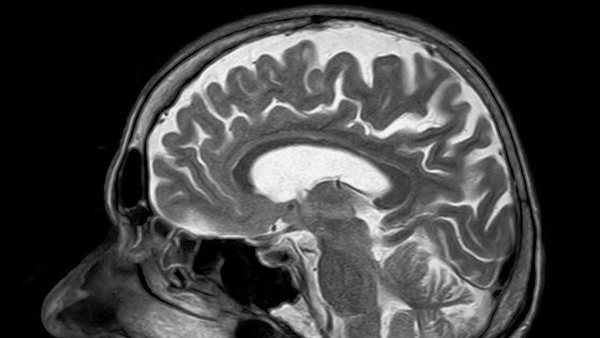

إدارة الغذاء والدواء توافق على عقار جديد لعلاج الفصام الدواء الجديد لمرض الفصام معروف باسم كوبينفي، هو أول دواء يؤخذ عن طريق الفم لعلاج المرض والذي يستهدف ما يعرف بمستقبلات الكولين في الدماغ بدلا من مستقبلات الدوبامين، التي كانت محور العلاج التقليدي.

الفصام هو اضطراب عقلي يتميز باضطرابات في التفكير، ويمكن أن يغير الإدراك والعواطف والتفاعلات الاجتماعية، ويسبب أعراض ذهانية أكثر حدة، بما في ذلك الهلوسة مثل سماع الأصوات، وصعوبة التحكم في الأفكار والشك في الآخرين، وذلك وفقًا لهيئة الغذاء والدواء.

السبب الدقيق للفصام غير معروف، لكنَّ معظم الخبراء يعتقدون أن سبب هذه الحالة هو مزيج من العوامل الوراثية والبيئية، كما يمكن أن تؤدي بعض المواقف إلى حدوث هذه الحالة مثل: أحداث الحياة المجهدة، أو إساءة استخدام الأدوية.